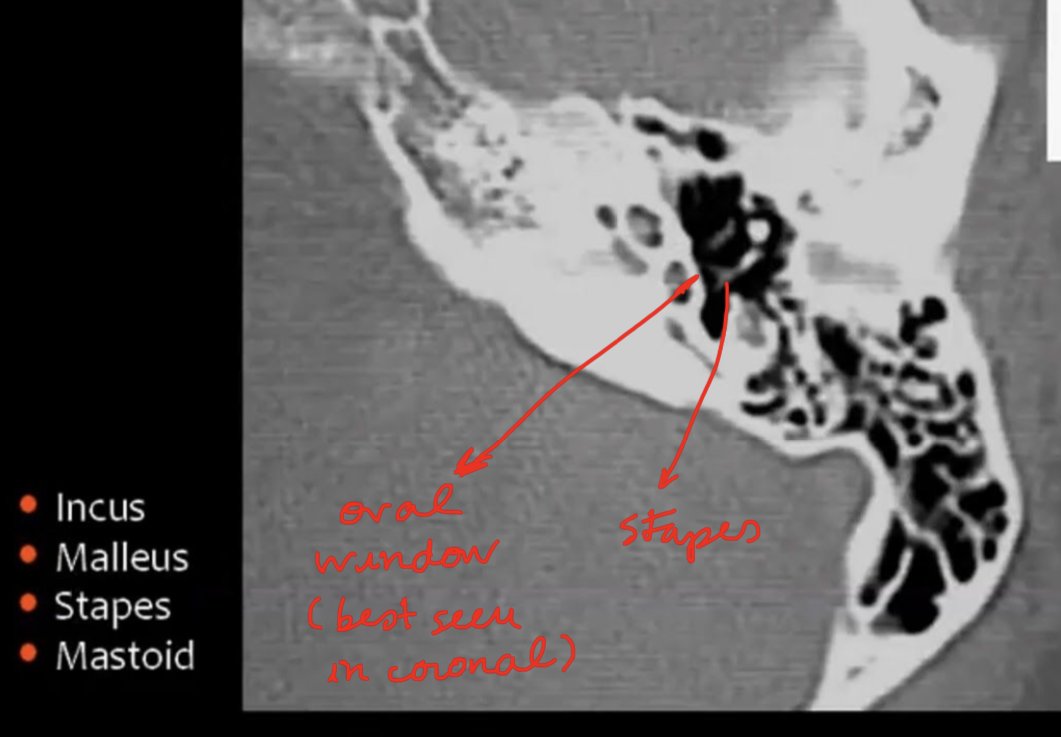

What are the ossicules of middle ear?

Description?